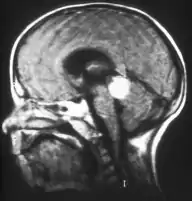

Inherited forms of retinoblastomas are more likely to be bilateral. In addition, inherited uni- or bilateral retinoblastomas may be associated with pineoblastoma and other malignant midline supratentorial primitive neuroectodermal tumors (PNETs) with a dismal outcome; retinoblastoma concurrent with a PNET is known as trilateral retinoblastoma.[15] A 2014 meta-analysis showed that 5-year survival of trilateral retinoblastoma increased from 6% before 1995 to 57% by 2014, attributed to early detection and improved chemotherapy.[16]

In about two-thirds of cases,[27] only one eye is affected (unilateral retinoblastoma); in the other third, tumors develop in both eyes (bilateral retinoblastoma). The number and size of tumors on each eye may vary. In certain cases, the pineal gland or the suprasellar or parasellar region (or in very rare cases other midline intracranial locations) is also affected (trilateral retinoblastoma). The position, size, and quantity of tumors are considered when choosing the type of treatment for the disease.

Aspect of trilateral retinoblastoma on MRI

Traditional ultrasound B scan can detect calcifications in the tumour while high-frequency ultrasound B scan is able to provide higher resolution than the traditional ultrasound and determine the proximity of the tumour with front portion of the eye. MRI scan can detect high-risk features such as optic nerve invasion; choroidal invasion, scleral invasion, and intracranial invasion. CT scan is generally avoided because radiation can stimulate the formation of more eye tumours in those with RB1 genetic mutation.[35]